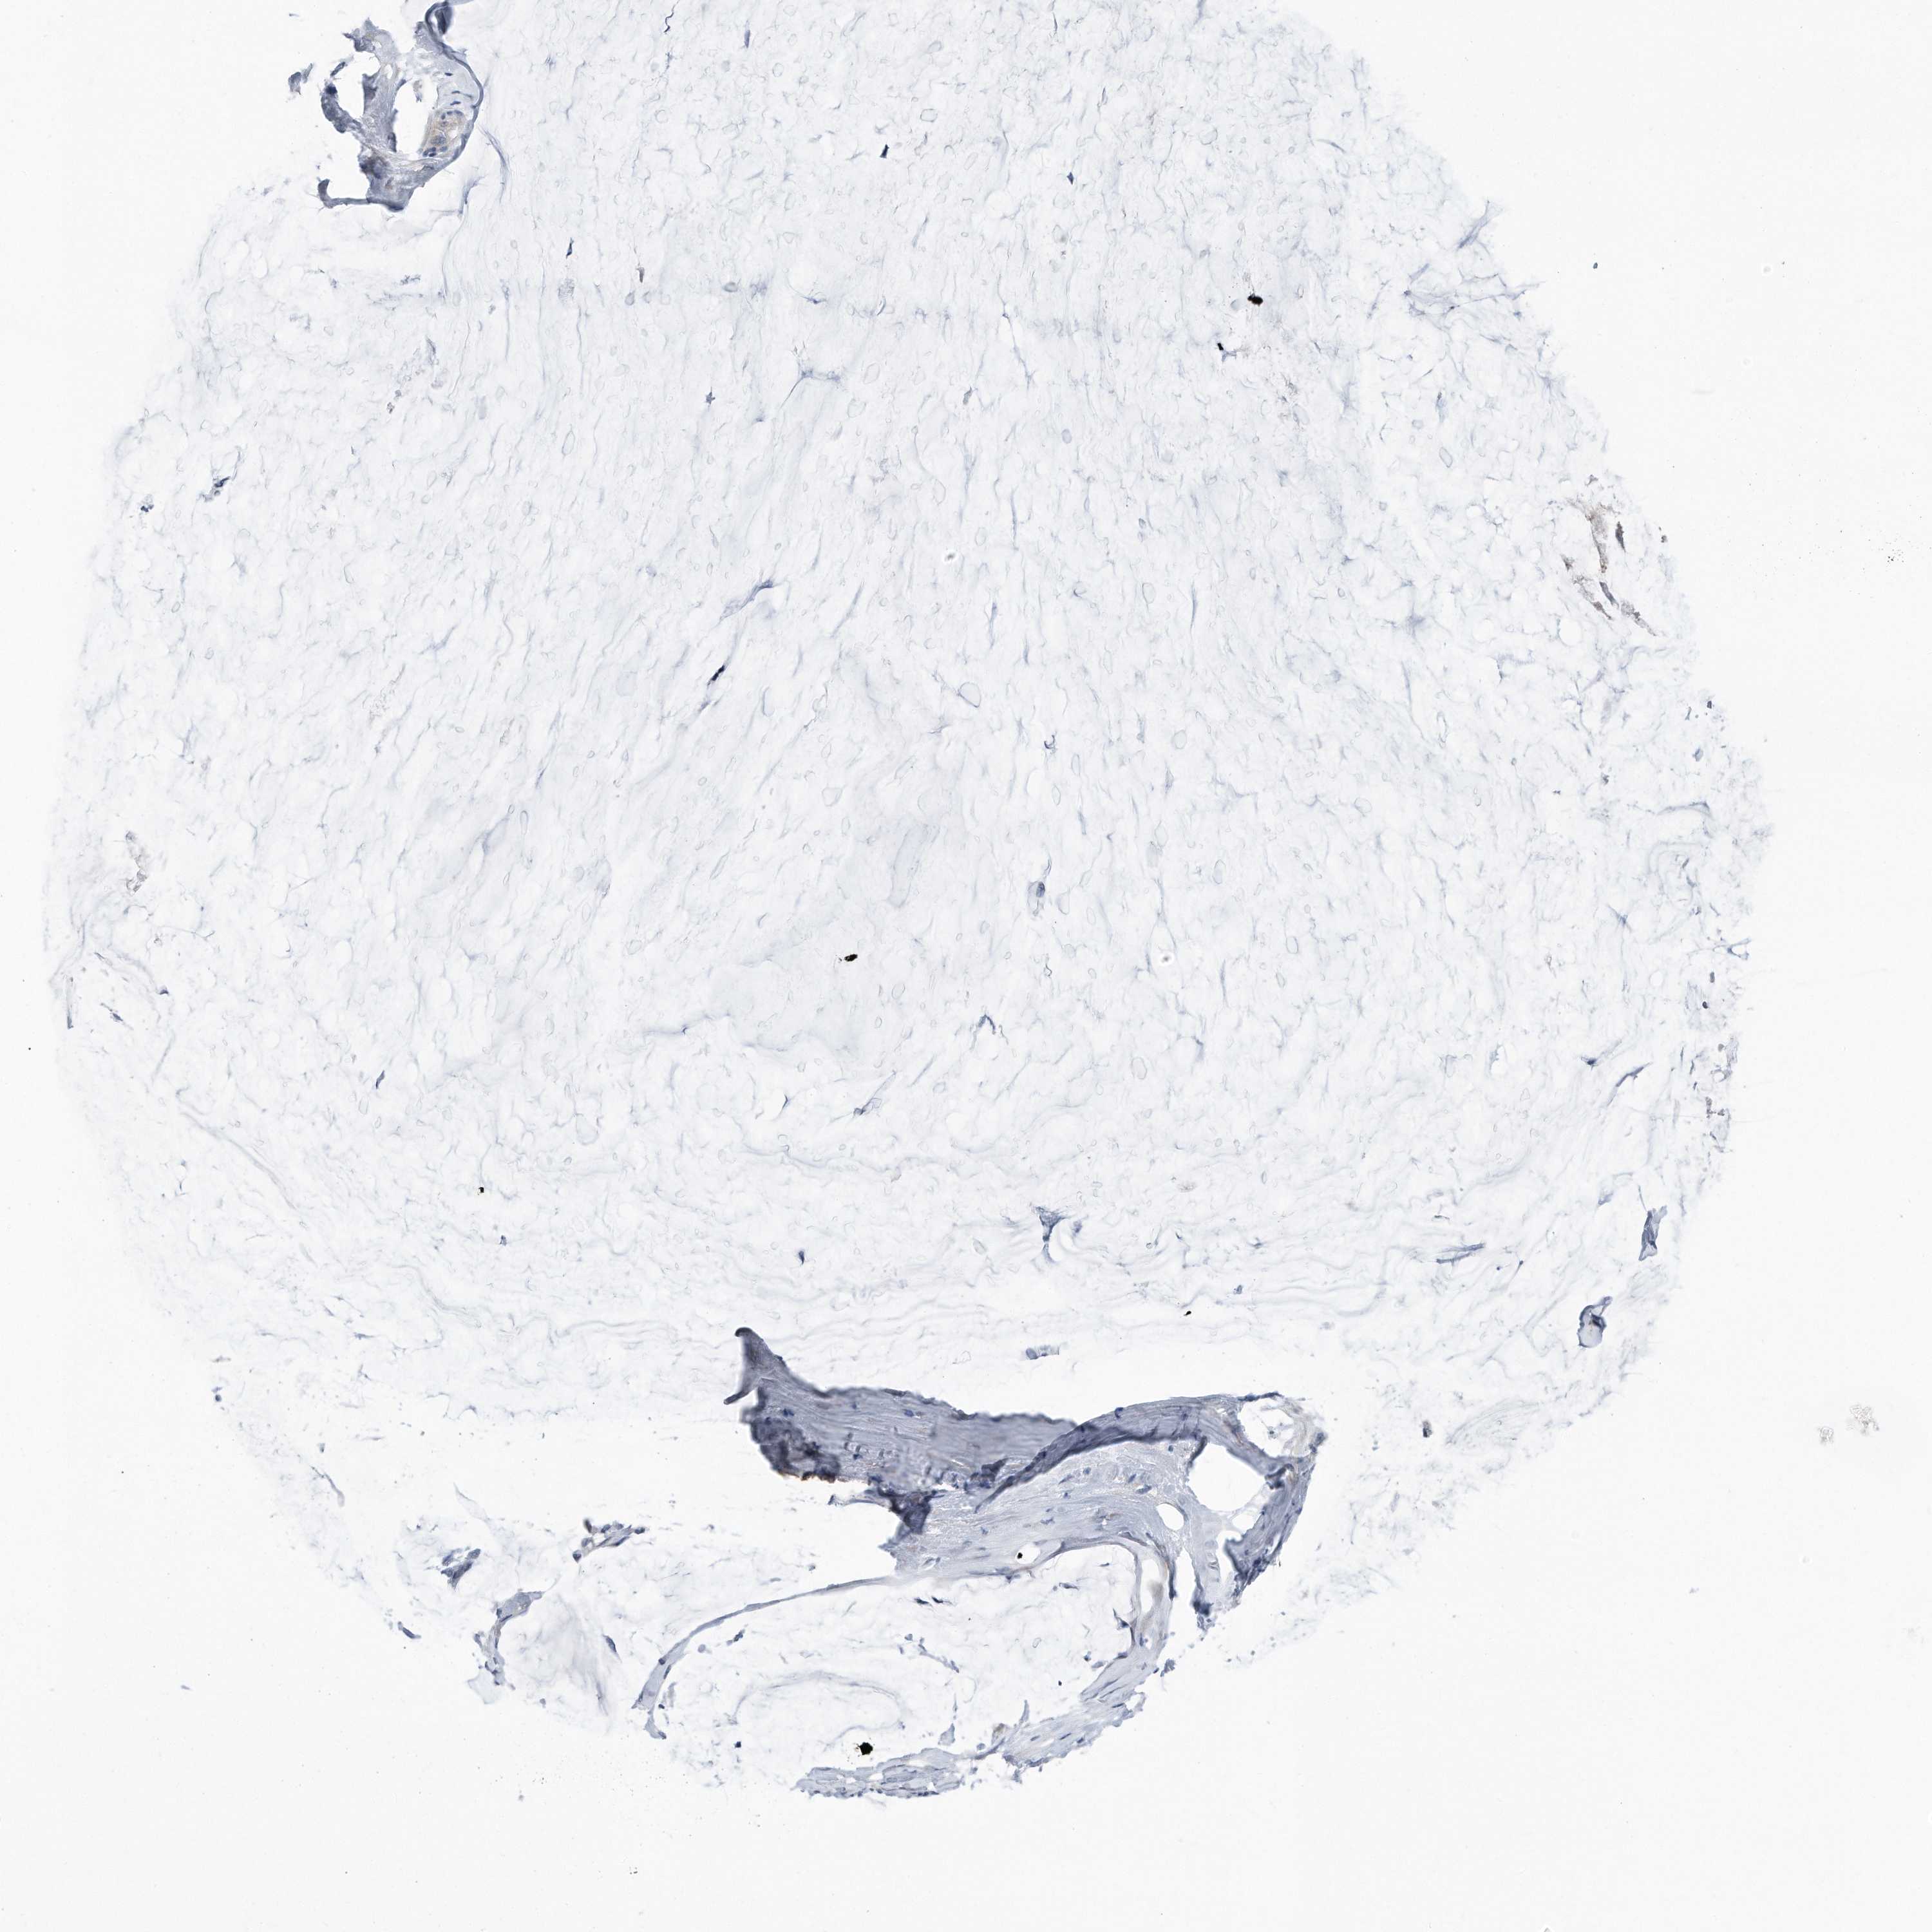

OVARIAN CANCER - Protein expressioni

A mouse-over function shows sample information and annotation data. Click on an image to view it in a full screen mode. Samples can be filtered based on level of antibody staining by selecting one or several of the following categories: high, medium, low and not detected. The assay and annotation is described here.

Note that samples used for immunohistochemistry by the Human Protein Atlas do not correspond to samples in the TCGA dataset.

Antibody stainingi

Antibody staining in the annotated cell types in the current human tissue is reported as not detected, low, medium, or high, based on conventional immunohistochemistry profiling in selected tissues. This score is based on the combination of the staining intensity and fraction of stained cells.

Each image is clickable and will lead to virtual microscopy that enables deeper exploration of all samples and also displays staining intensity scores, fraction scores and subcellular localization as well as patient and tissue information for each sample.

Antibody HPA030147

Staining

High

Medium

Low

Not detected

Intensity

Strong

Moderate

Weak

Negative

Quantity

>75%

75%-25%

<25%

None

Location

Nuclear

Cytoplasmic/membranous

Cytoplasmic/membranous,nuclear

Cystadenocarcinoma, serous, NOS

Carcinoma, endometroid

Cystadenocarcinoma, mucinous, NOS

Carcinoma, NOS